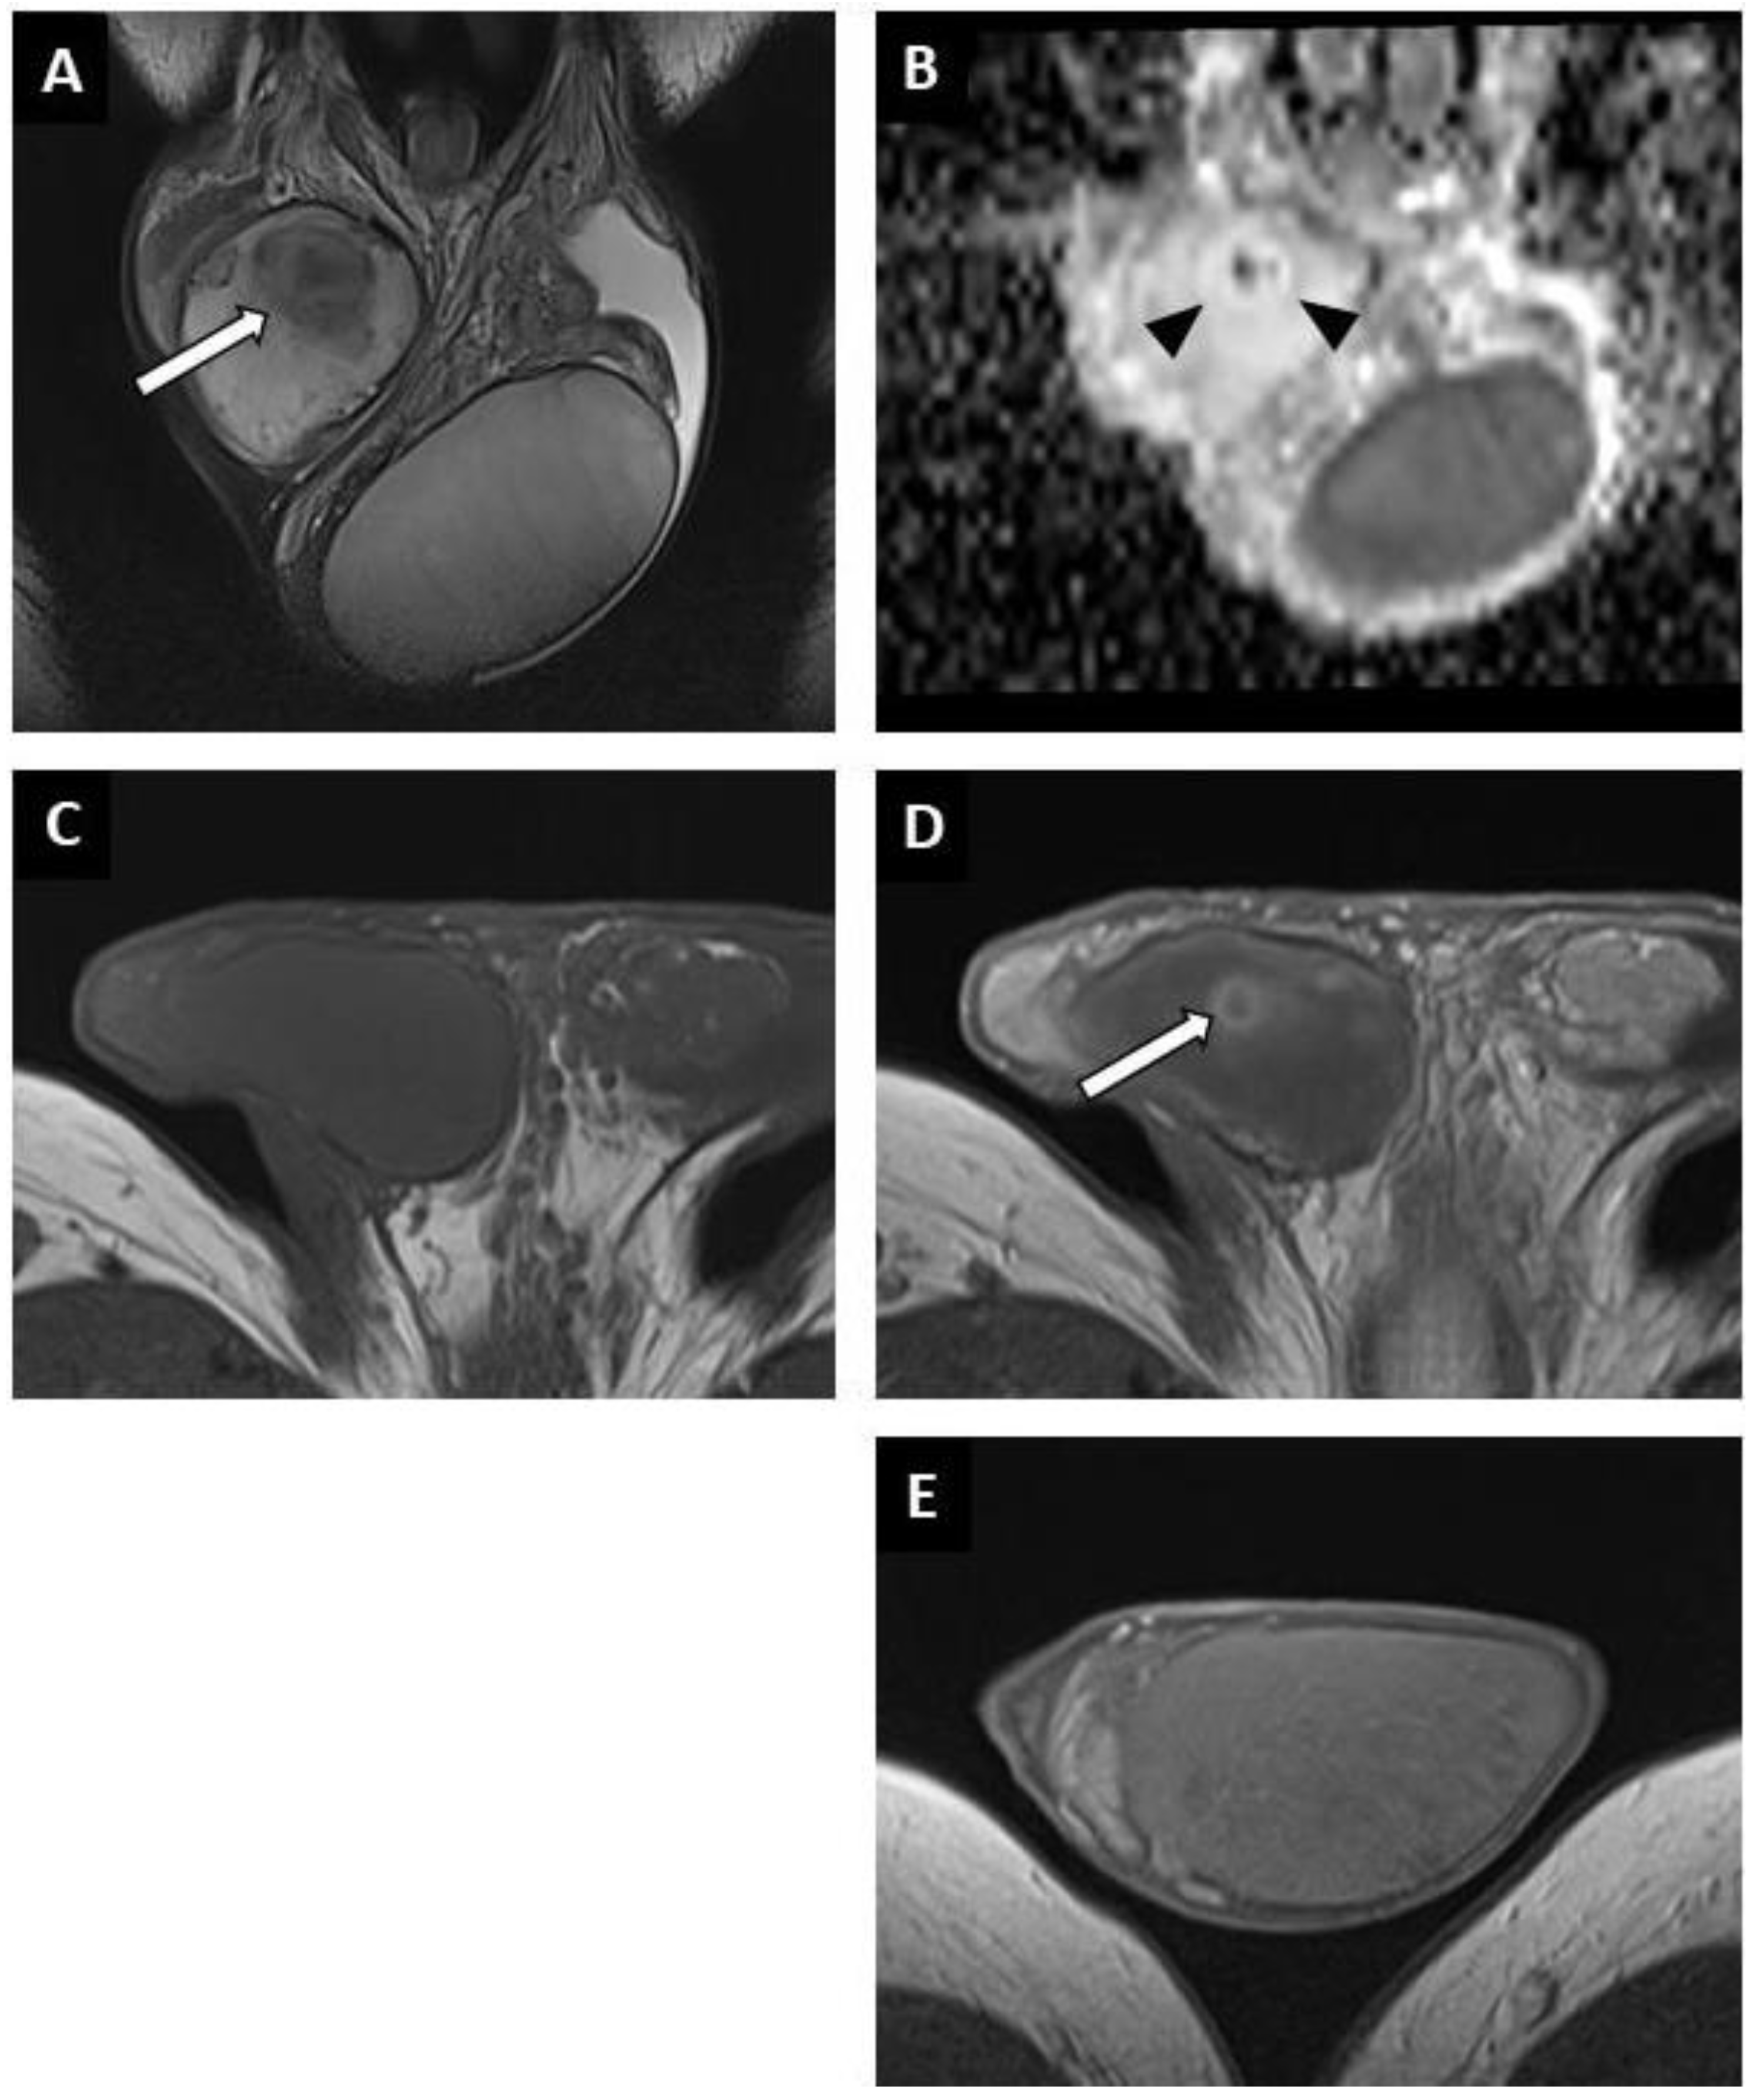

Figure 3. BOTT of the right testis in a 41-year-old man (infertility screening). Transverse B-mode US showed an ill-delineated hypoechoic nodular area (A). With colour Doppler US, the hypoechoic nodule was frankly hypovascular upon Ultrasensitive Doppler (B). CEUS demonstrated a hypo-enhanced (white arrowheads) area in concordance with the B-mode nodule (note that even the adjacent testis parenchyma was also poorly enhanced) (C). SWE map showed an area of increased stiffness in concordance with B-mode nodule (D). MRI axial T2W image showing a nodule with a hypo-intense signal (white arrow) (E). ADC map of the diffusion sequence demonstrated a focal area with an elevated ADC value compared with the contralateral testis (F). After the intravenous injection of gadolinium chelate, an area of reduced enhancement of the nodule was visible (G). Nodule enhancement followed the yellow time–signal-intensity curve (type 1) and the contralateral parenchyma corresponded to the purple one (H).

Lesions appeared as hypoechoic nodular areas (Figure 2 and Figure 3) for 44 patients (91.7%) and an entire hypoechoic testis infiltration for 4 (8.3%). The lesion was singular in 36 patients (75%), there were 2 nodules in 3 patients (6.3%) and more than 2 in 9 patients (18.8%). Conventional US findings results are summarized in Table 2.

All lesions had ill-delineated margins. In 42 cases (87.5%), the lesions appeared hypovascular compared to normal parenchyma (Figure 2 and Figure 3). In six patients, a hypervascular nodule with sharp boundaries was found within (four cases) or peripheral to (two cases) a hypovascular nodular area using CDUS, and corresponded to residual seminomas upon pathological analysis. One patient, who was finally diagnosed with a partially regressed seminoma, had no focal US abnormality that was suggestive of a viable tumour.

Twenty-five CEUS were performed. A reduced vascularity of the entire testis, which was more pronounced in the hypoechoic region, was visible for 22 patients (Figure 3C). In three cases, corresponding to patients with hypervascular nodules in CDUS, an early and strongly enhanced small nodule was visible, surrounded by an area of reduced enhancement in two cases, and at its periphery in one case. Few microbubbles were observed within the hypovascular lesions in all cases.

SWE exhibited a focal area of increased stiffness (Figure 2B and Figure 3D) corresponding to hypoechoic lesions in 37 of 40 patients (92.5%). In three patients (7.5%) there was no detectable focal stiffness abnormality. Stiffness measurements in 30 patients indicated a mean value of 13.7 ± 8.4 kPa in areas of elevated stiffness versus 2.6 ± 1.3 kPa in normal testicular parenchyma (significant difference, p < 0.01). The mean stiffness ratio was 5.3 ± 2.4. No significant difference was found when comparing hypervascular nodules and the hypovascular surrounding areas in the case of partial tumour regression.

BOTTs appeared as round or oval nodules (81%) (Figure 3 and Figure 4) or a focal area with irregular boundaries (19%) on the T2 sequences (hyposignal). No lesions were visible on the T1 sequences (isosignal) (Figure 4C).

The diffusion-weighted sequences showed nodular areas of reduced signal with increased ADC values (mean value: 2 ± 0.3 × 10−3 mm2/s) (Figure 2E and Figure 3F) compared to contralateral parenchyma (mean value: 1.3 ± 0.3 × 10−3 mm2/s) in all patients (significant difference, p < 0.01). The mean ADC ratio was 1.6 ± 0.3. Within these areas with increased ADC values, a restrictive nodule (Figure 4B) was detected in six of the seven patients that were diagnosed with a partially regressed testicular tumour.

Dynamic contrast-enhanced sequences showed areas of reduced enhancement in all cases. The size of this area matched that of the lesion on the T2 sequences (Figure 3G) in 11 patients (26.2%), and in 31 patients (73.8%) it overlapped the lesion with reduced enhancement extending to the peripheral parenchyma (Figure 2F and Figure 4D). In the cases of partial tumour regression, dynamic contrast-enhanced sequences revealed early and strongly enhanced focal abnormalities within areas of reduced enhancement, corresponding to nodules in six patients (Figure 4D), and an ill-delineated area with increased enhancement in one (corresponding to the patient in whom no focal abnormality that was suggestive of a viable tumour was found upon US examination).

Time–signal-intensity curves were created (Figure 3H) for 23 patients with complete tumour regression, showing type 0 curves in 7 cases and type 1 in 16 cases. Type 2 (two patients) or 3 (five patients) time–signal-intensity curves were observed in focal lesions corresponding to viable seminoma.